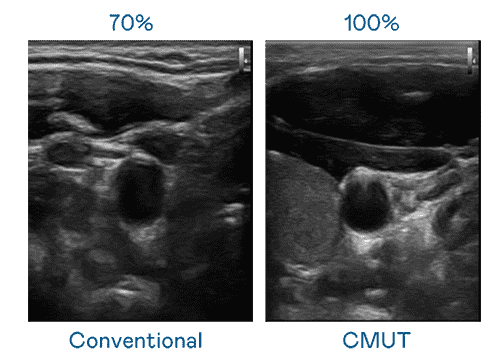

CMUT 技术是一种用电容式微机电元件来产生超音波讯号的技术。。与传统 PZT 压电式技术相比,,,,CMUT 频宽增加 30%,,更宽频的超音波讯号让影像解析度大幅提升,,是实现高影像品质医疗超音波扫描、、促进精准医疗发展的关键技术。。。

大频宽带来超清晰影像

超音波影像的解析度高低,,,,首先取决于探头能发出的讯号频宽。。。欧陆注册 CMUT 可提供高清晰的超音波讯号,,,,提供高频宽、、、高灵敏度、、、、影像纹理细节更高的超音波影像,,,,协助医护人员缩短影像判读时间及利用精准的医疗影像进行诊断。。。